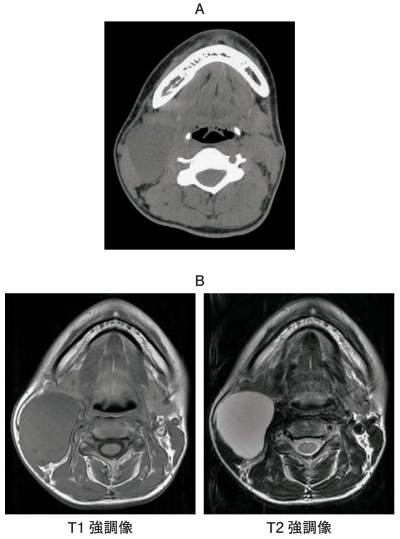

下顎レベルのCT、MRI T1 強調像およびT2 強調像を別に示す。右側頸部の病変で考えられるのはどれか。1つ選べ。

a. 鰓囊胞

b. 脂肪腫

c. 線維腫

d. 多形腺腫

e. 甲状舌管囊胞